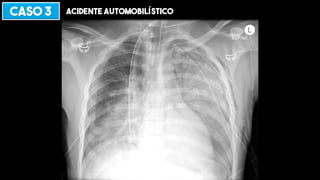

CASO 3 ACIDENTE AUTOMOBILÍSTICO